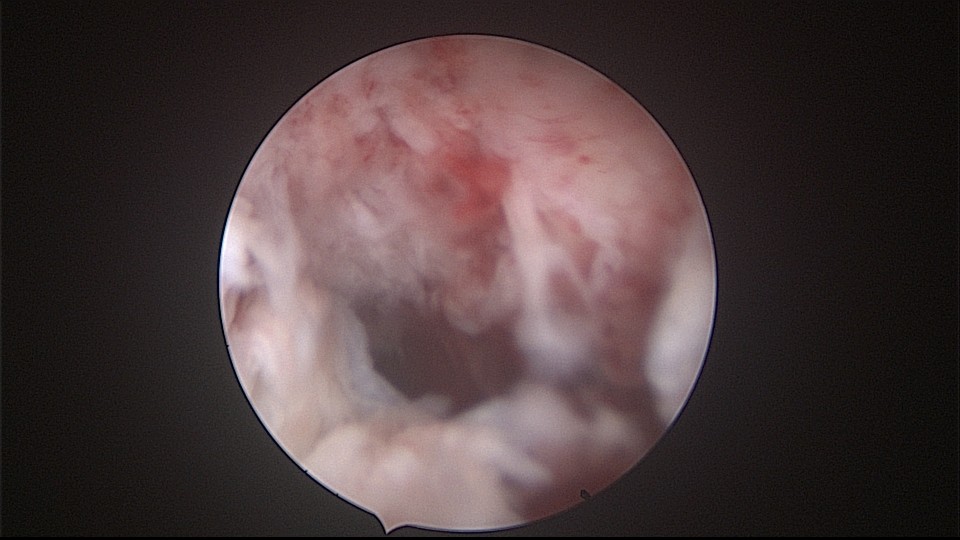

患者52岁,G2P1,顺产1次。安环27年,外院取环失败。病人肥胖,子宫极度前倾前屈位,宫腔镜见宫颈管组织杂乱,宫颈管上段右前壁见假道,膨宫不良,视野模糊,寻找宫腔方向困难,准备B超监护过程中,拆走扩阴器,腹部下压子宫,终于寻找到了宫颈内口,看到了爱母环下端,异物钳牵拉出节育环,再次探查宫腔,无其他异常。